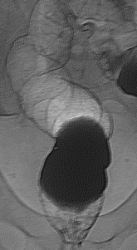

Чудесное двойное контрастирование. Дивертикулез нисходящей ободочной кишки.Кровотечение из дивертикула рядовое явление. Вопрос - почему нет снимка с двойным контрастированием слепой кишки, а только снимки с тугим выполнением?

А Вас не смущает задняя стенка, ампулярного отдела, прямой кишки?

Похоже на небольшой дефект с неровными контурами...неужели "малый" рак? Дело в том, что при попытке увеличения Ваших снимков их размер практически не изменяеется...дивертикулы то видны хорошо, а вот с прямой кишкой я "промахнулся", может сделать размер чуть больше...

Вы правы!!! Рак прямой кишки, малая форма.

Здравствуйте Анатолий Владимирович, вообще мой учитель, отмечал настороженность на ректо-сигмоидный отдел прямой кишки, на углы(печеночный, селезеночный) и восходящий отдел ободочной кишки, об этом всегда помню и делаю снимки прицельные с предворительным вывидением на контуры, в продемонстрированном случае органической патологии прямой кишки и видимого дивертикулеза больше ни чего не визуализируется. Данный случай тоже не просто так выложил, малая форма очень редко встречается, обычно когда уже всё запущено или приличных размеров.

В данном случае большую роль сыграли онколог с пальцевым исследованием прямой кишки и эндоскопист с взятием биоптата, так что от меня только формальность-в последнюю очередь. По поводу красной стрелки это пузырьки газа с отграничением контраста, а то что указано стрелкой скорее всего остаточная перистальтика, на остальных снимках нет чего такого подобного, да и под скопией такое очень заметно.